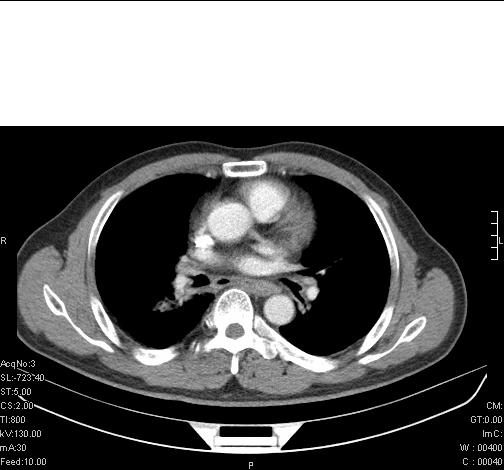

标题: CT6685:右肺阻塞性炎症,增强CT。

前几天,发了患者的平扫片,患者抗炎一周后增强扫描。右中叶病灶吸收明显,但下叶病灶未见明显吸收。右肺门可见结节影,看来凶多吉少

右肺下叶支气管管腔狭窄,管壁增厚,右下肺见斑片状高密度影,考虑右侧肺门中心肺癌伴阻塞性肺炎

右肺下叶散在的斑片状致密影,下叶支气管变窄。考虑:右肺慢性炎症。

右肺下叶支气管壁明显增厚,考虑癌症并阻塞性炎症、肺门淋巴结肿大

考虑右肺癌并阻塞性炎症、肺门淋巴结肿大

右肺下叶支气管壁不规则增厚,右肺下叶有斑片状影分布。考虑右肺中央型肺癌伴右肺下叶阻塞性改变。建议支纤镜检查。平扫比增强较好显示了病变情况。

右主支气管狭窄,管壁增厚。考虑右中心性肺ca伴阻塞性肺炎。

既然抗炎治疗有效,可继续治疗;右肺下叶支气管管腔狭窄,管壁增厚,右下肺见斑片状高密度影,右侧主支气管后见结节影(淋巴结?),肺癌不能排出。